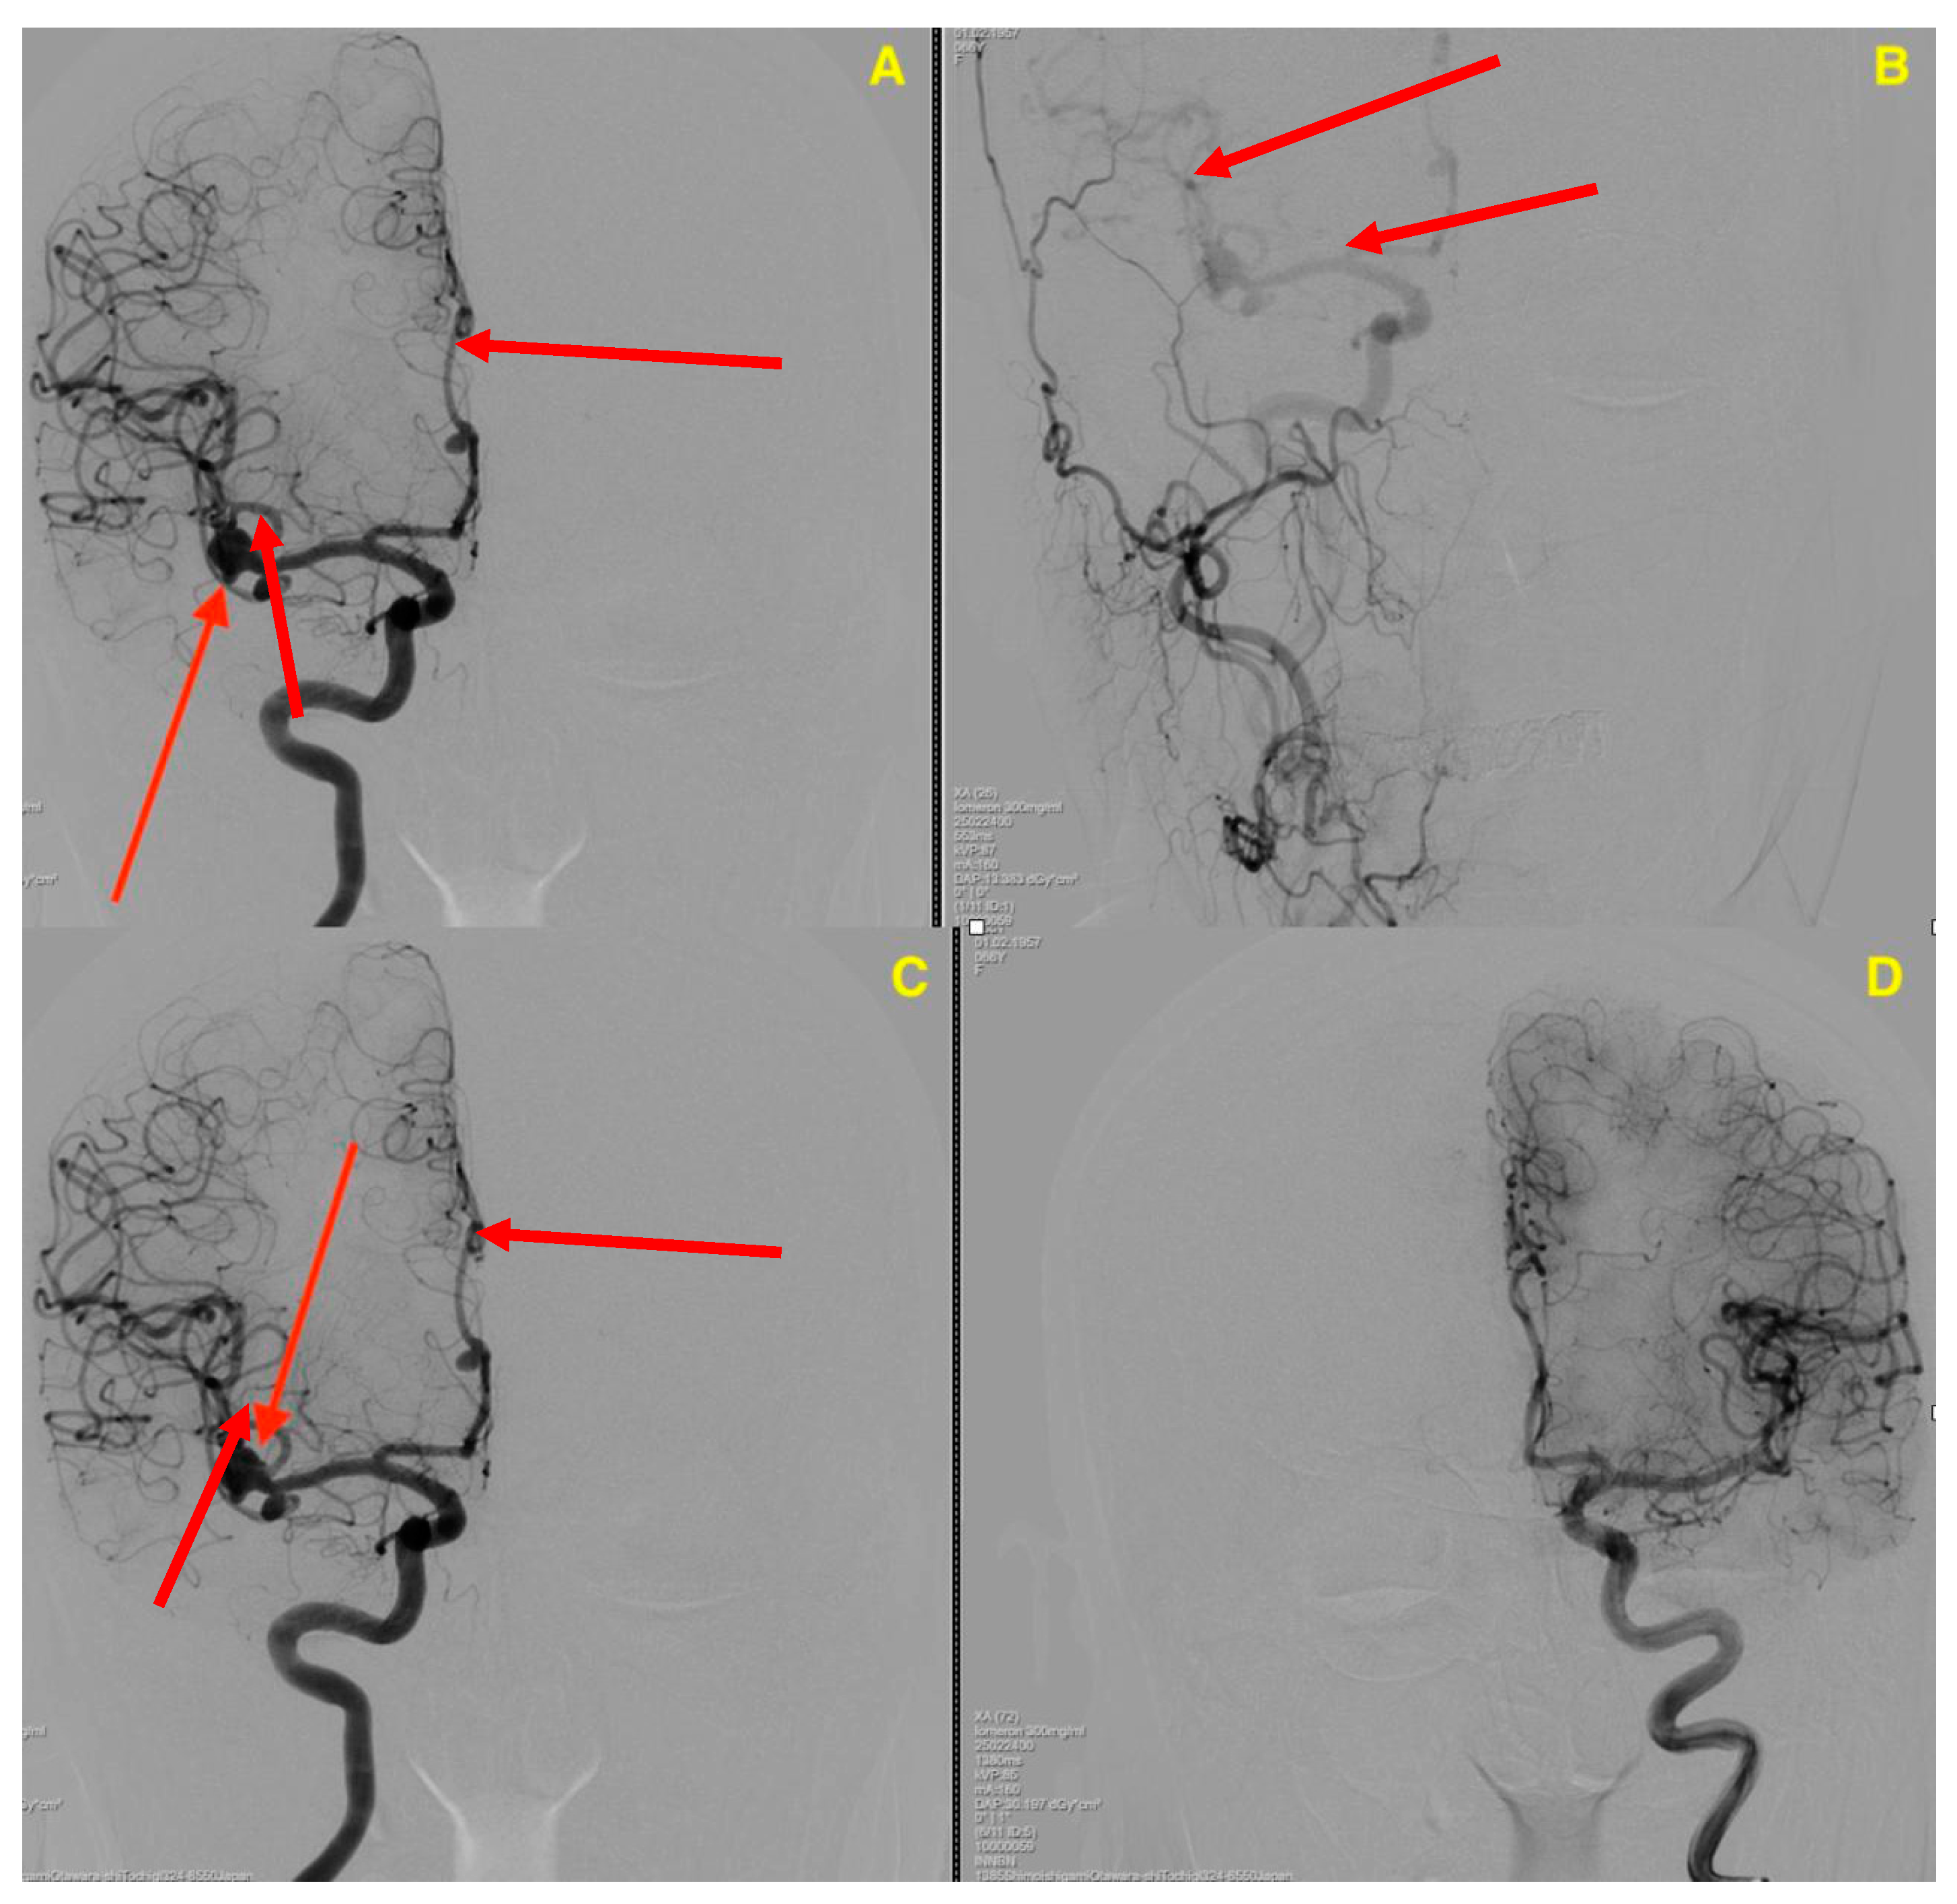

2. Case Presentation